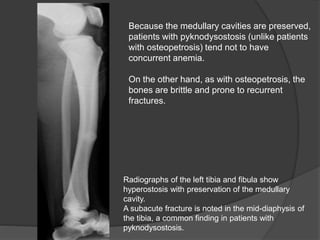

Radiographs of the left tibia and fibula show

hyperostosis with preservation of the medullary

cavity.

A subacute fracture is noted in the mid-diaphysis of

the tibia, a common finding in patients with

pyknodysostosis.

Because the medullary cavities are preserved,

patients with pyknodysostosis (unlike patients

with osteopetrosis) tend not to have

concurrent anemia.

On the other hand, as with osteopetrosis, the

bones are brittle and prone to recurrent

fractures.